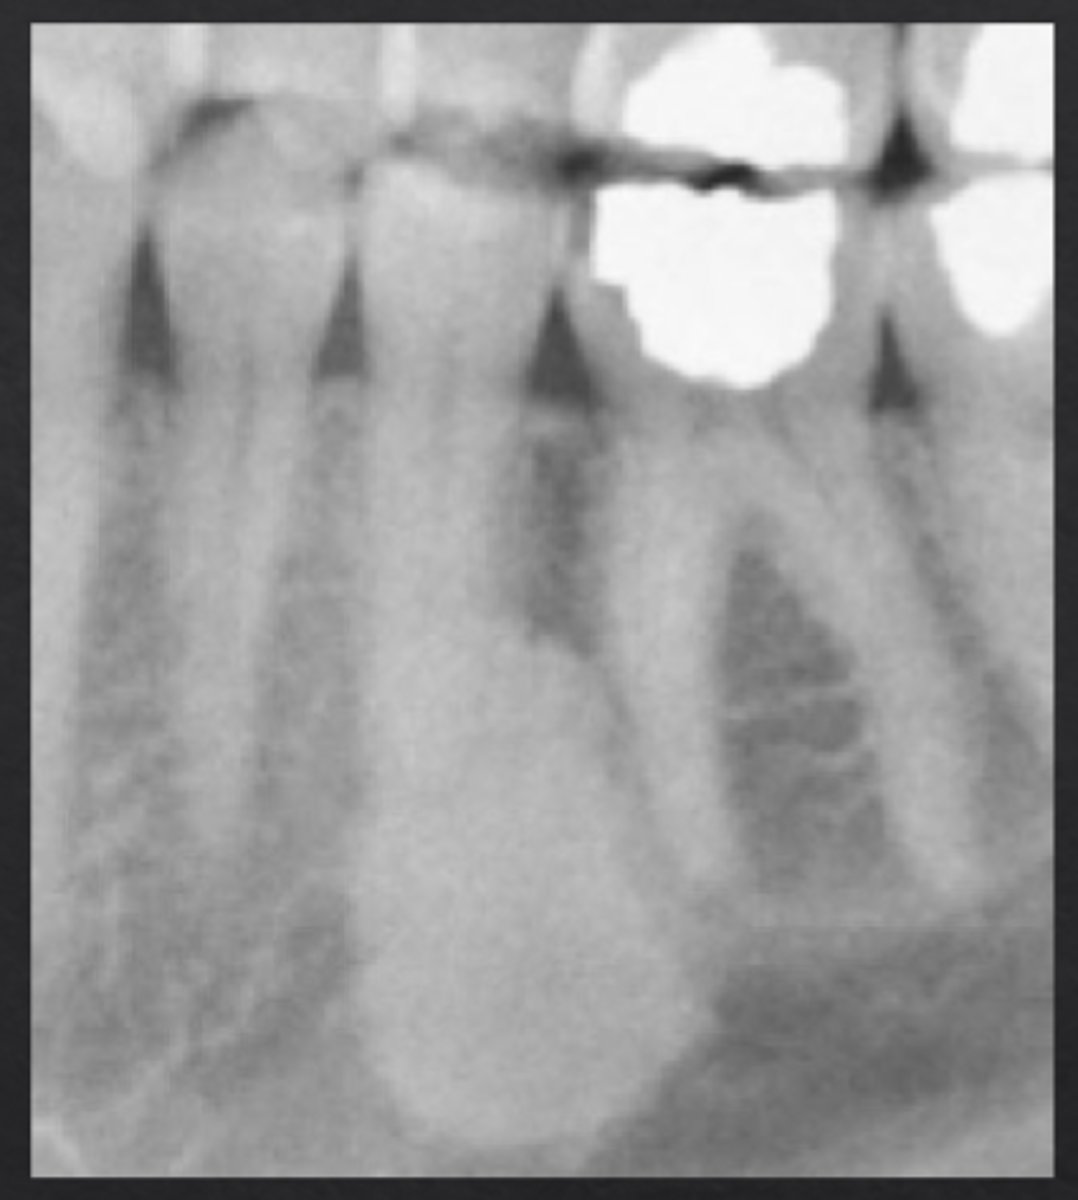

What is cemento-osseous dysplasia?

Localized bone dysplasia that becomes more calcified over time

Cemento-Osseous Dysplasia: _____ if located in one sextant, _____ if located in more than one sextant

Focal, florid

How does cemento-osseous dysplasia appear radiographically?

Preapical radiolucency with central calcifications, will become more calcified over time (may lose radiolucent rim)